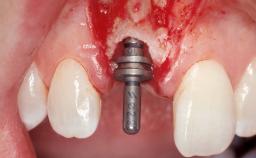

Immediate Placement of an Implant in a Maxillary Left Central Incisor Site

A 33-year-old female patient presented with an upper left central incisor that required extraction after a failed endodontic therapy. The tooth had been traumatized when the patient was a teenager and had undergone several endodontic treatments, including two apicectomy procedures. The patient was in good health and did not smoke. Clinical examination showed that the patient had a high lip line. In full smile, the gingival margins of the upper teeth were visible to the first molars. The gingival margins of central incisors 11 and 21 were only just showing. Examination of tooth 21 confirmed that the tooth was mobile and had hypererupted by 1 mm.

Placement Protocol Immediate implant placement

Tooth Site Maxillary incisor or canine

Socket Morphology Single-root socket

Socket Integrity Damage to one or more bone walls